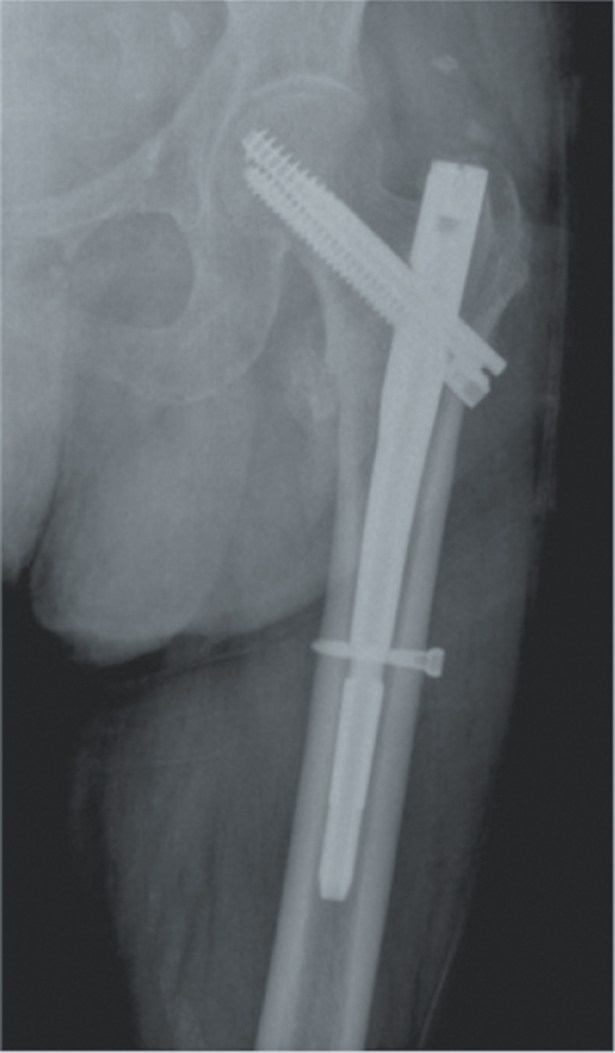

Methods: In this retrospective study, a total of 314 patients who were operated on for hip fractures were included study. Patients were then divided into four groups based in their implant types: long-stem cementless bipolar hemiarthroplasty (n = 124; 102 female, 22 male; mean age = 84.2 ± 6.4 years), standard-stem cementless bipolar hemiarthroplasty (n = 74; 48 female, 26 male; mean age = 83.5 ± 6.9 years), antegrade intertrochanteric nail (n = 61; 35 female, 26 male; mean age = 78.5 ± 6.8 years), and total hip arthroplasty (n = 55; 34 female, 21 male; mean age = 72.5 ± 4.3 years). Data including gender, age, duration from injury to surgery, American Society of Anesthesiologists (ASA) score, comorbidities, use of antiplatelet agents, Barthel Index of Activities of Daily Living, type of anesthesia, operation time, preoperative hemoglobin values, blood transfusions given, duration of hospital stay, complications, and type of fracture were recorded.

Abstract Image